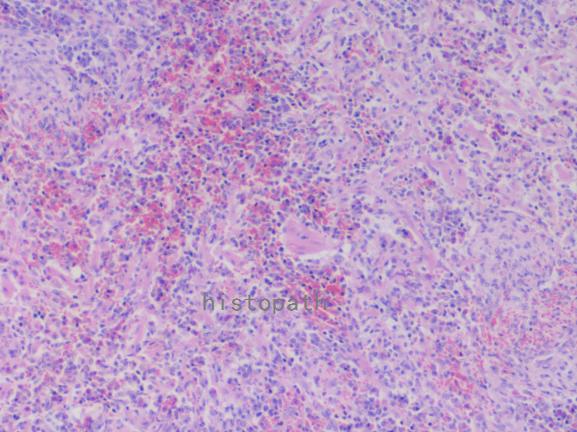

苏木精--伊红染色法(hematoxylin-eosin staining),简称HE染色法,石蜡切片技术里常用的染色法之一。苏木精染液为碱性,主要使细胞核内的染色质与胞质内的核酸着紫蓝色;伊红为酸性染料,主要使细胞质和细胞外基质中的成分着红色。HE染色法使组织学、胚胎学、病理学教学与科研中最基本、使用最广泛的技术方法。

染色结果:

细胞核呈蓝色,细胞质、肌肉、结缔组织、红细胞、嗜曙红颗粒呈不同程度的粉红色。钙盐、软骨基质和各种微生物也可染成蓝色或紫蓝色。核仁呈红色。着色情况不仅与组织或细胞的种类有关,也随其生活周期及病理变化而改变。质量优良的HE染色切片样本,细胞核与细胞质蓝红对比明显,胞核鲜明,核膜及核染色质颗粒均清晰可见。